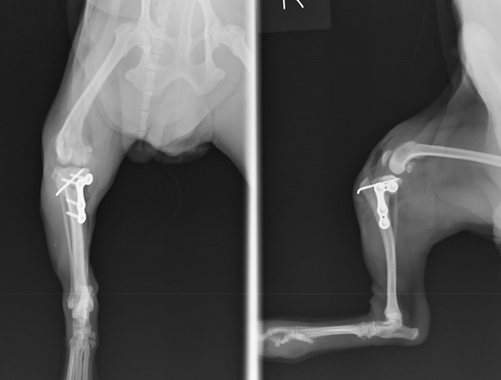

症例:10歳 ヨークシャーテリア 去勢オス

症状:3日前から急に右後足を挙上、跛行するとのことで来院。触診、レントゲン検査にて前十字靭帯断裂症が強く疑われました。

脛骨が前方に変位し、ファットパットサイン(関節炎)所見も認められます。

まず半円形に骨を切断できる特殊なブレードを使用して脛骨の骨きりを行います。

L字型の特殊プレートを使用して、角度を補正して骨きりした部分の固定を行います。

最後に膝蓋骨内方脱臼整復手術を同時に行い、手術終了としました。

術後レントゲンです。体重のかかる脛骨高平角が水平に近づきました。これなら体重をかけても痛みはほとんどでないと判断されます。